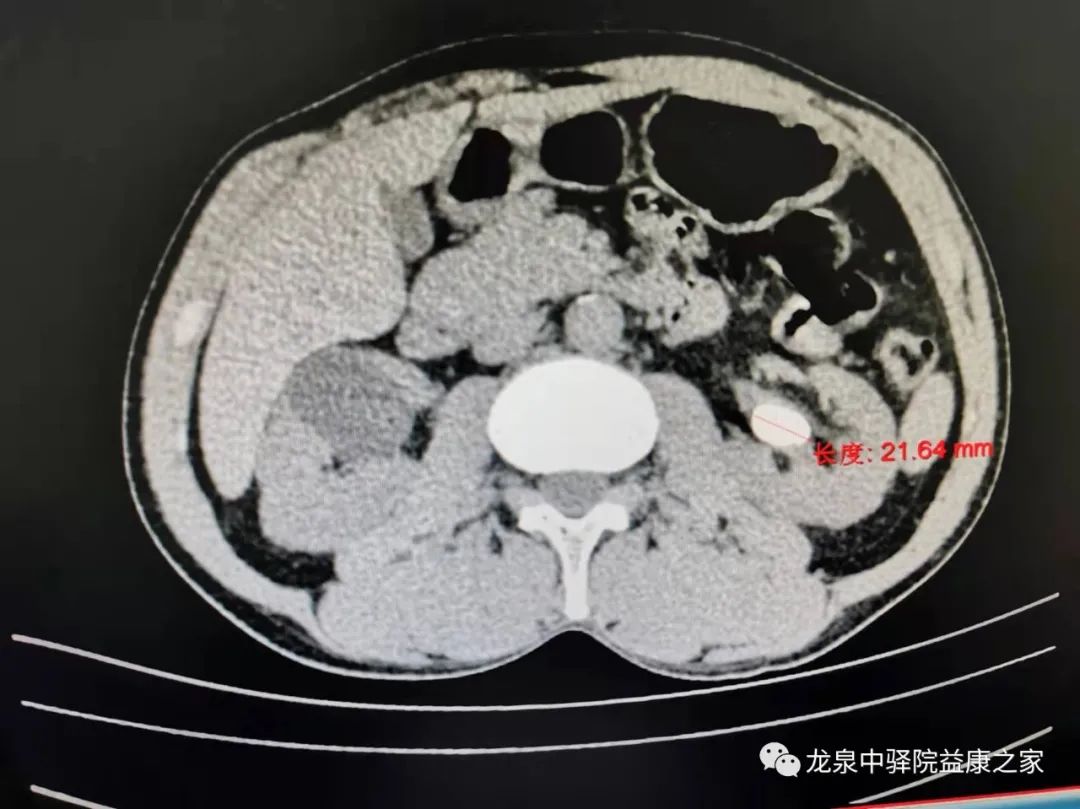

曾文彤教授无积水肾结石经皮肾手术术前CT阅片指导。

教学讨论中,曾主任一一解答了科室医生提出的问题,进一步明确诊断、制定治疗方案,并对无积水肾结石手术提出了指导建议。

讲座结束后,曾文彤教授现场对一例无积水型肾铸形结石患者进行了现场会诊,详细指导患者的综合治疗方案和经皮肾镜手术技术要点;